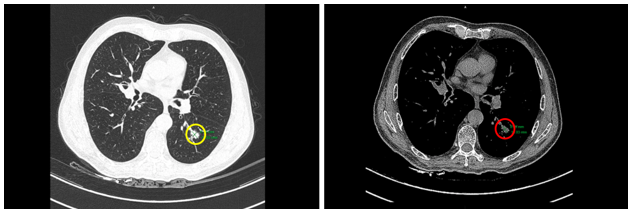

-         Chụp cắt lớp vi tính (CT) ngực:

Hình 1: Hình ảnh nốt đặc thùy dưới phổi trái kích thước 10x14mm trên của sổ nhu mô (vòng tròn màu vàng) và cửa sổ trung thất (vòng tròn màu đỏ)

Hình 2: Hình ảnh hạch trung thất ở cửa sổ chủ phổi (vòng trong màu đỏ), kích thước 8x11mm, mất cấu trúc rốn hạch

Hình 4: Hình ảnh tổn thương u phổi thùy dưới phổi trái kích thước 10x15mm trên CT (vòng tròn màu vàng) và PET/CT (vòng tròn màu đỏ) tăng chuyển hóa FDG (SUVmax: 9,8)

Hình 5: Hình ảnh hạch trung thất ở cửa sổ chủ phổi đường kính 7mm trên CT (vòng tròn màu vàng) và PET/CT (vòng tròn màu đỏ) tăng chuyển hóa FDG (SUVmax: 2,69)